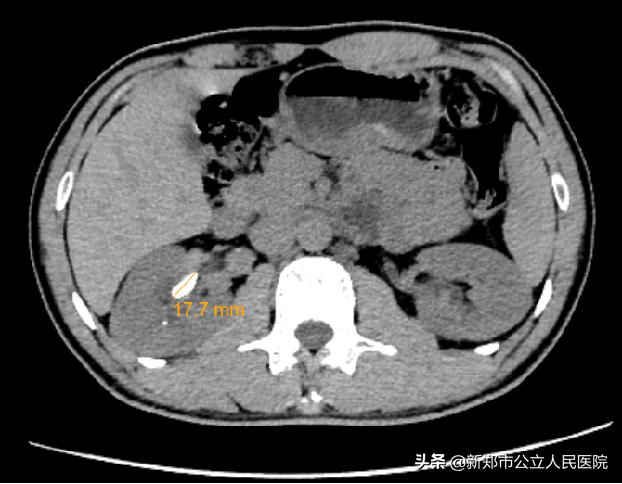

泌尿外科副主任牛俊豪接诊后完善相关检查后,诊断为右侧肾盂结石。CT结果显示:右侧肾盂最大结石直径约为17.7毫米。